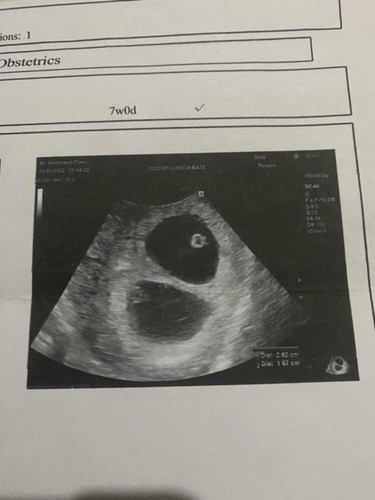

ตั้งครรภ์แฝดอัลตราซาวด์เจอเมื่อตอนหกสัปดาห์

ซาวด์ตอน 6 วีค หมอเจอถุงตั้งครรภ์สองใบอีกถุงนึงมีตัวเด็กแล้วแต่อีกถุงนึงยังไม่มีเสียงหัวใจ มีโอกาสมากน้อยแค่ไหนคะที่จะเห็นเสียงหัวใจอีกหนึ่งดวง มีแม่ๆคนไหนเจอเหตุการณ์แบบนี้บ้างคะ